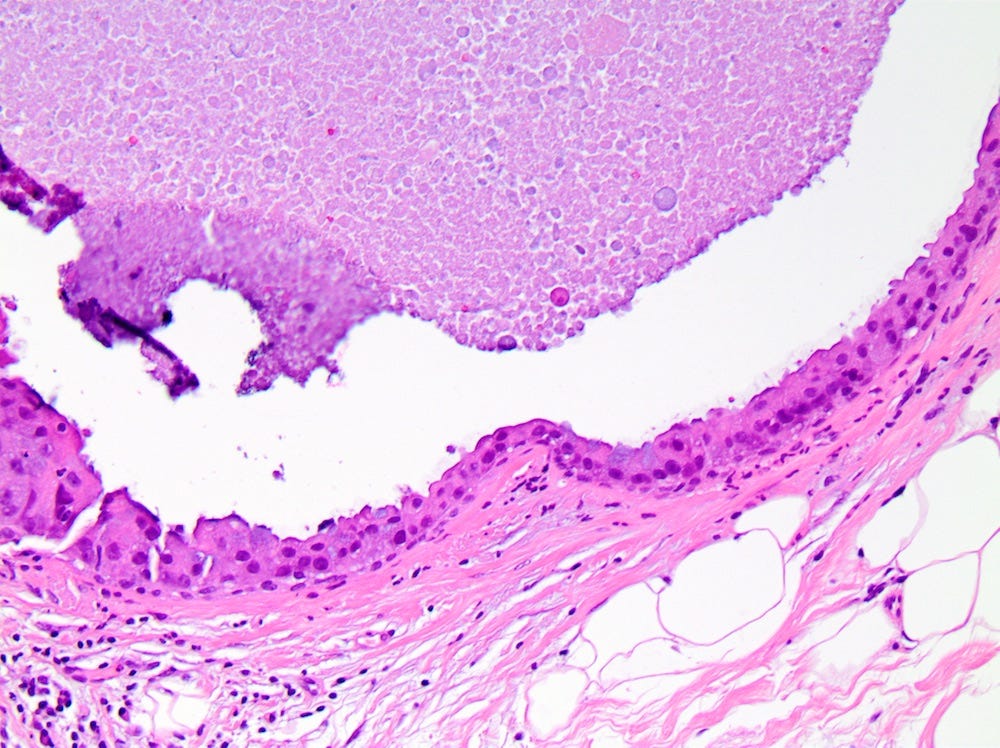

Ductal carcinoma in situ (DCIS) is a neoplastic proliferation of breast ductal epithelial cells within the ductal-lobular system with malignant microscopic features but without evidence of invasion through the epithelial basement membrane or myoepithelial cell layer into the surrounding stroma.

DCIS includes a heterogeneous group of lesions in terms of microscopic appearance, molecular alterations, biomarker expression profile and biologic potential for progression to invasive carcinoma. It is divided into low grade (less aggressive) DCIS and high grade DCIS. Normal breast tissue appears to transform to only one of these entities through two distinct molecular pathways (i.e. high grade DCIS does not typically arise from low grade DCIS). Low grade DCIS shows frequent chromosomal losses at 16q. High grade DCIS shows frequent losses at 8p and gains at 17q and has a similar molecular profile as invasive breast cancer.

The microcalcifications that identify DCIS on mammograms are a response to cell death from either a hypoxic environment (the Warburg effect) or cell crowding due to abnormal cells growing unchecked inside the duct. When these calcifications appear on a mammogram, they often have suspicious features that require further investigation.

DCIS - microscopic images